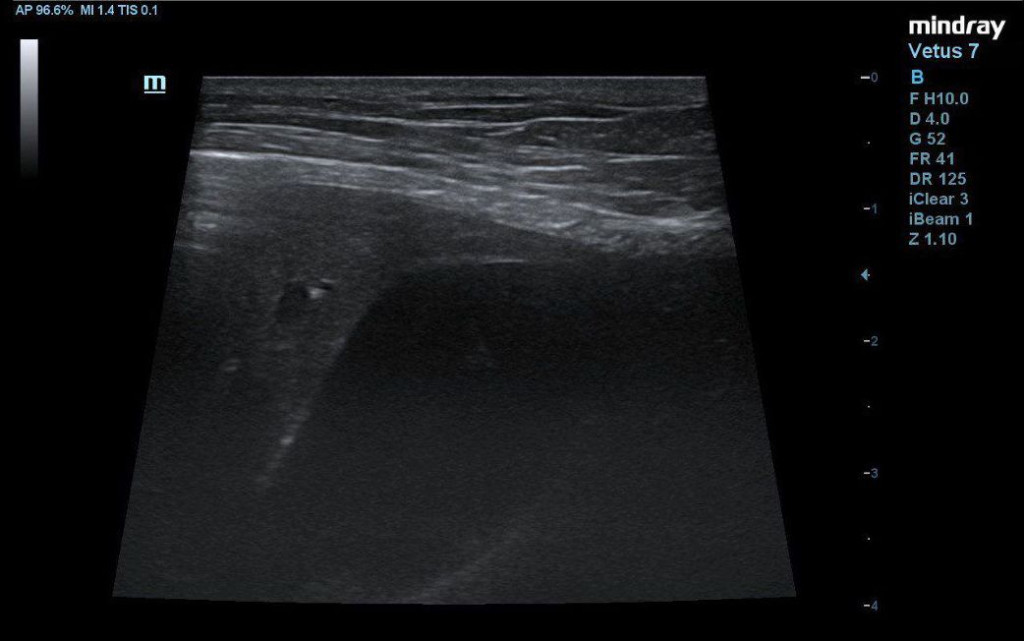

- каплевидная форма желчного пузыря с анэхогенным содержимым и скудным количеством гипоэхогенной взвеси (рис. 3);